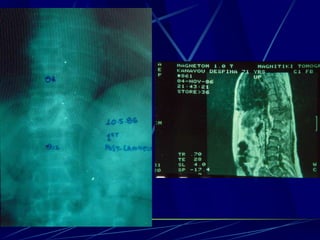

Φυματίωση της σπονδυλικής στήλης